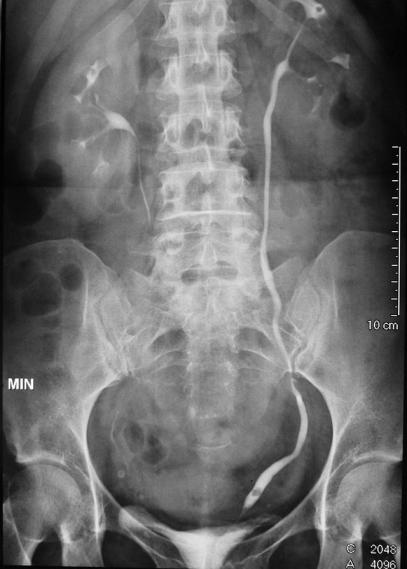

Der Operateur geht mit einem feinen Instrument mit Kamera (Endoskop) über die Harnröhre in die Harnblase ein und kann dann weiter über die Harnleiter in die ableitenden Harnwege der Niere gelangen. Mit dem Endoskop ist es dem Arzt möglich Auffälligkeiten in den genannten Organen zu erkennen und/oder kleine Eingriffe (z.B. Entfernung noch Nierensteinen, Zerkleinerung von Nierensteinen mittels Laser, Entnahme von Proben) vorzunehmen. Häufig wird zur genaueren Beurteilbarkeit der Harntrakt mittels Kontrastmittel und Röntgenbildern dargestellt. Dank modernster Technik ist die Strahlenbelastung hierbei sehr gering.

In manchen Fällen wird im Rahmen des Eingriffs eine Harnleiterschiene („Doppel-J-Schiene“) eingelegt, welche ein schmerzhaftes Zuschwellen des Harnleiters verhindert. Diese verläuft vom Nierenbecken über die Harnleiter in die Blase und ist von außen nicht sichtbar. Diese kann in der Regel nach wenigen Tagen bis Wochen durch Ihren Urologen ambulant (ohne Narkose) entfernt werden.